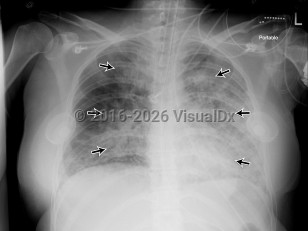

Acute respiratory distress syndromeAcute respiratory distress syndrome